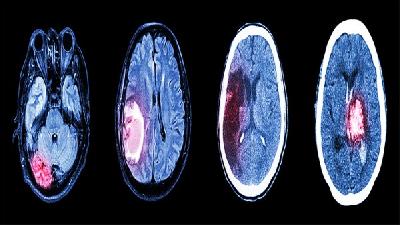

小儿脑瘫通常在出生后6个月至2岁之间可以确诊。小儿脑瘫的诊断主要依据运动发育迟缓、肌张力异常、姿势异常等临床表现...

新生儿脑瘫需通过体格发育评估、神经反射检查、影像学扫描及基因检测综合诊断。 1、发育评估 观察抬头翻身等动作是否...